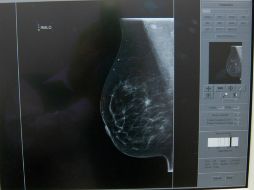

Tecnología Desarrollan en México chip para detectar cáncer de mama 25 de noviembre de 2014 - 10:17 hs Ciencia médica Cáncer de mama